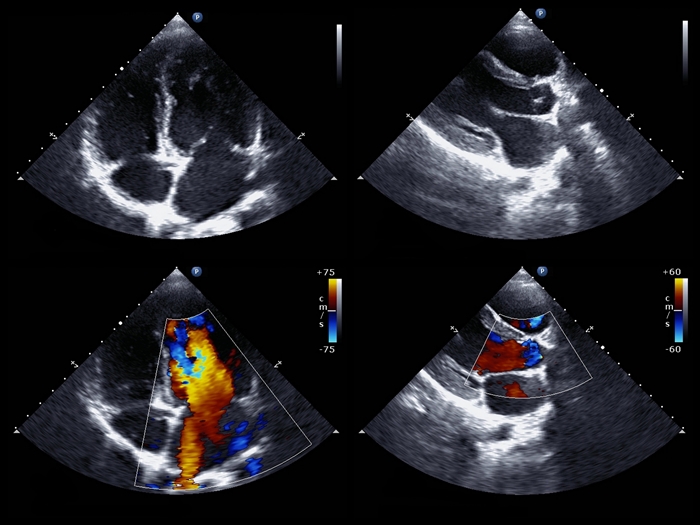

心エコー

現在心臓の画像検査では

基本的な検査の一つです。

↑写真のように

横になって機械を当てるだけの

簡単な検査ですが、

心臓の動き・形・弁膜症の有無や

その他の心臓の病気を

見つけるための重要な検査です。

心エコーの費用

9000円かかりますが、保険の1割〜3割負担で

900円〜2700円前後になります。

| 心エコー | 超音波(ちょうおんぱ)を使う検査です。横になって機械を当てるだけの簡単な検査です。 |